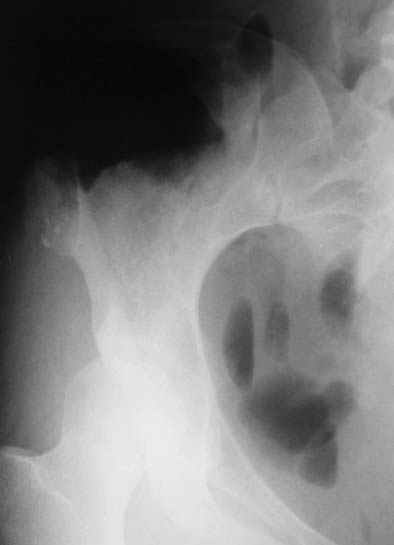

Уважаемые коллеги, больную прооперировали. После выделения остеохондрома резецирована в пределах неизменённой кости. Выявлено, что гребень подвздошой кости не пострадал от опухоли. В результате резекции сформирован сквозной дефект в крыле подвздошной кости треугольной формы 6х7х8 см. В качестве трансплантата использована наружная кортикальная пластинка заднего отдела крыла подвздошной кости.

Трансплантат фиксирован на месте дефекта при помощи шурупов и проволоки. Кровопотеря 550 мл.

На фото этапы операции, R-gr.